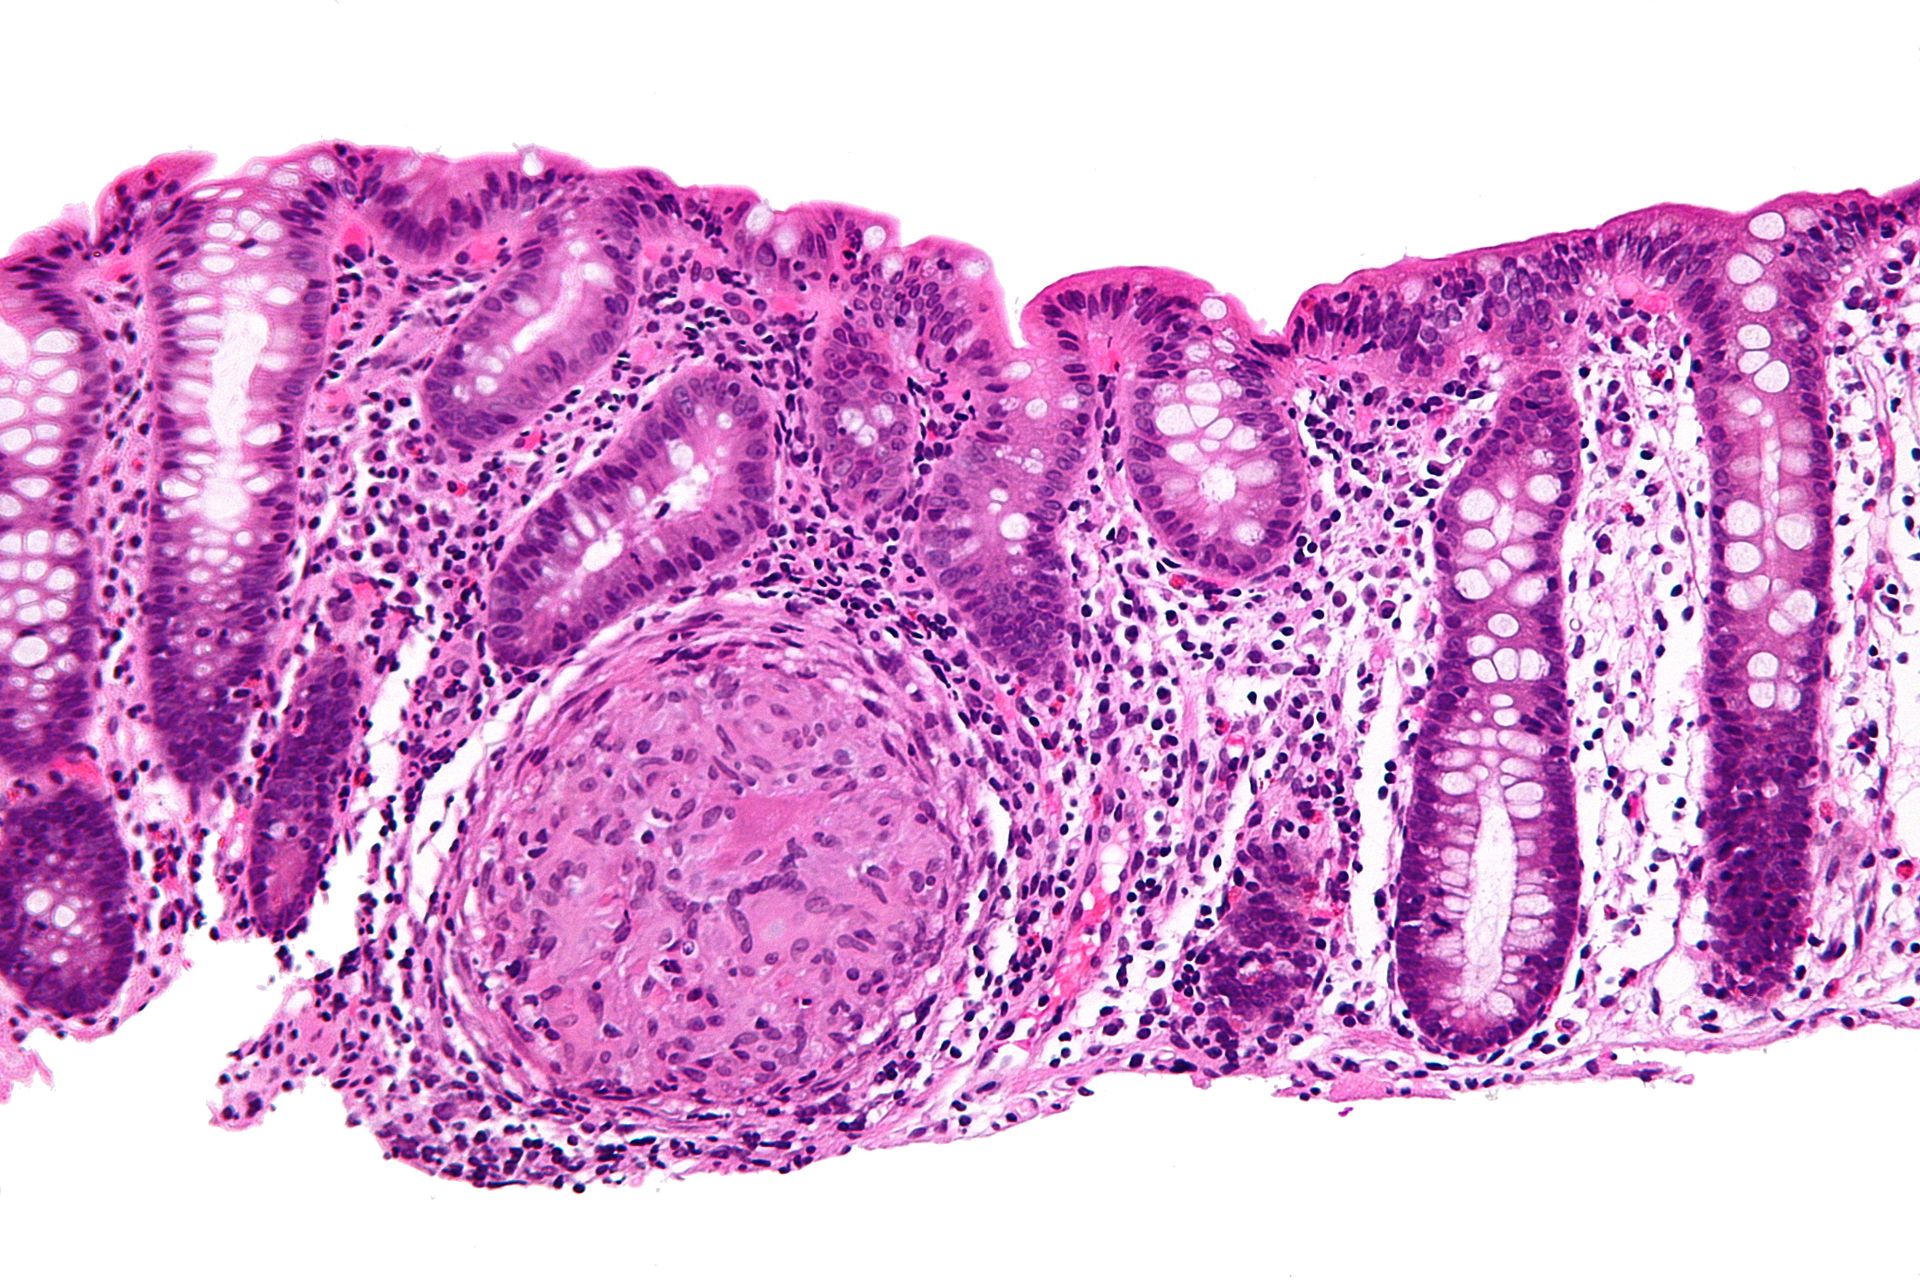

La enfermedad de Crohn es un proceso inflamatorio crónico del tracto intestinal, principalmente. Aunque puede afectar a cualquier parte del tracto digestivo desde la boca hasta el ano, afecta especialmente a la porción más baja del intestino delgado (íleon) o el intestino grueso (colon y recto). Se trata de una enfermedad inmunológica inflamatoria intestinal, y actualmente no se conoce con precisión porqué se desencadena.

2.- Biopsia endoscópica donde se puede apreciar inflamación granulomatosa del colon en un caso de enfermedad de Crohn.